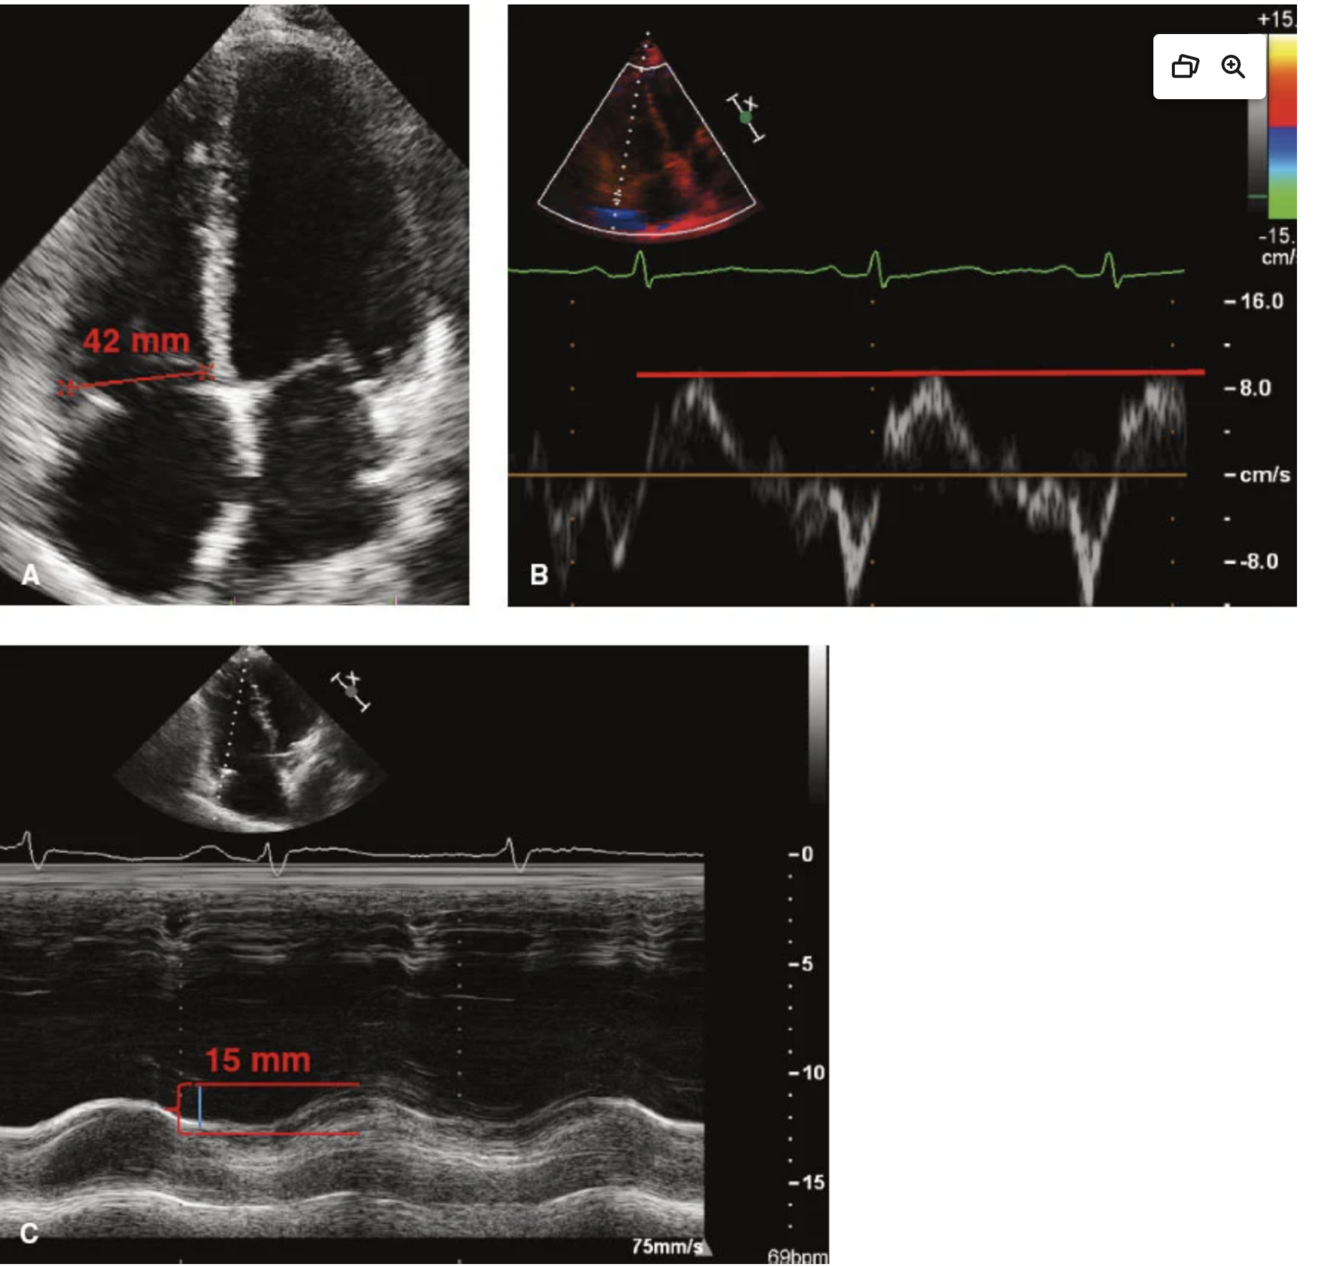

RV size and function in this patient?

This patient has an abnormal right ventricular size and systolic function. From the two-dimensional apical 4-chamber view of the right ventricle , the dimension of the right ventricle at the base measures 42 mm. This is larger than the normal cutoff of 41 mm at this level, indicating dilation. Alternatively, a dimension >35 mm at the mid-level in the right ventricular focused view would also indicate right ventricular dilation. With respect to right ventricular function, from the tissue Doppler images of the lateral tricuspid annulus , the tissue Doppler-derived tricuspid lateral annular systolic velocity or S’ velocity is less than the normal cutoff of 9.5 cm/s indicating systolic dysfunction. As well, the M-mode image through the lateral tricuspid annulus or TAPSE is also <17 mm, which is consistent with the S’ velocity indicating right ventricular systolic dysfunction.